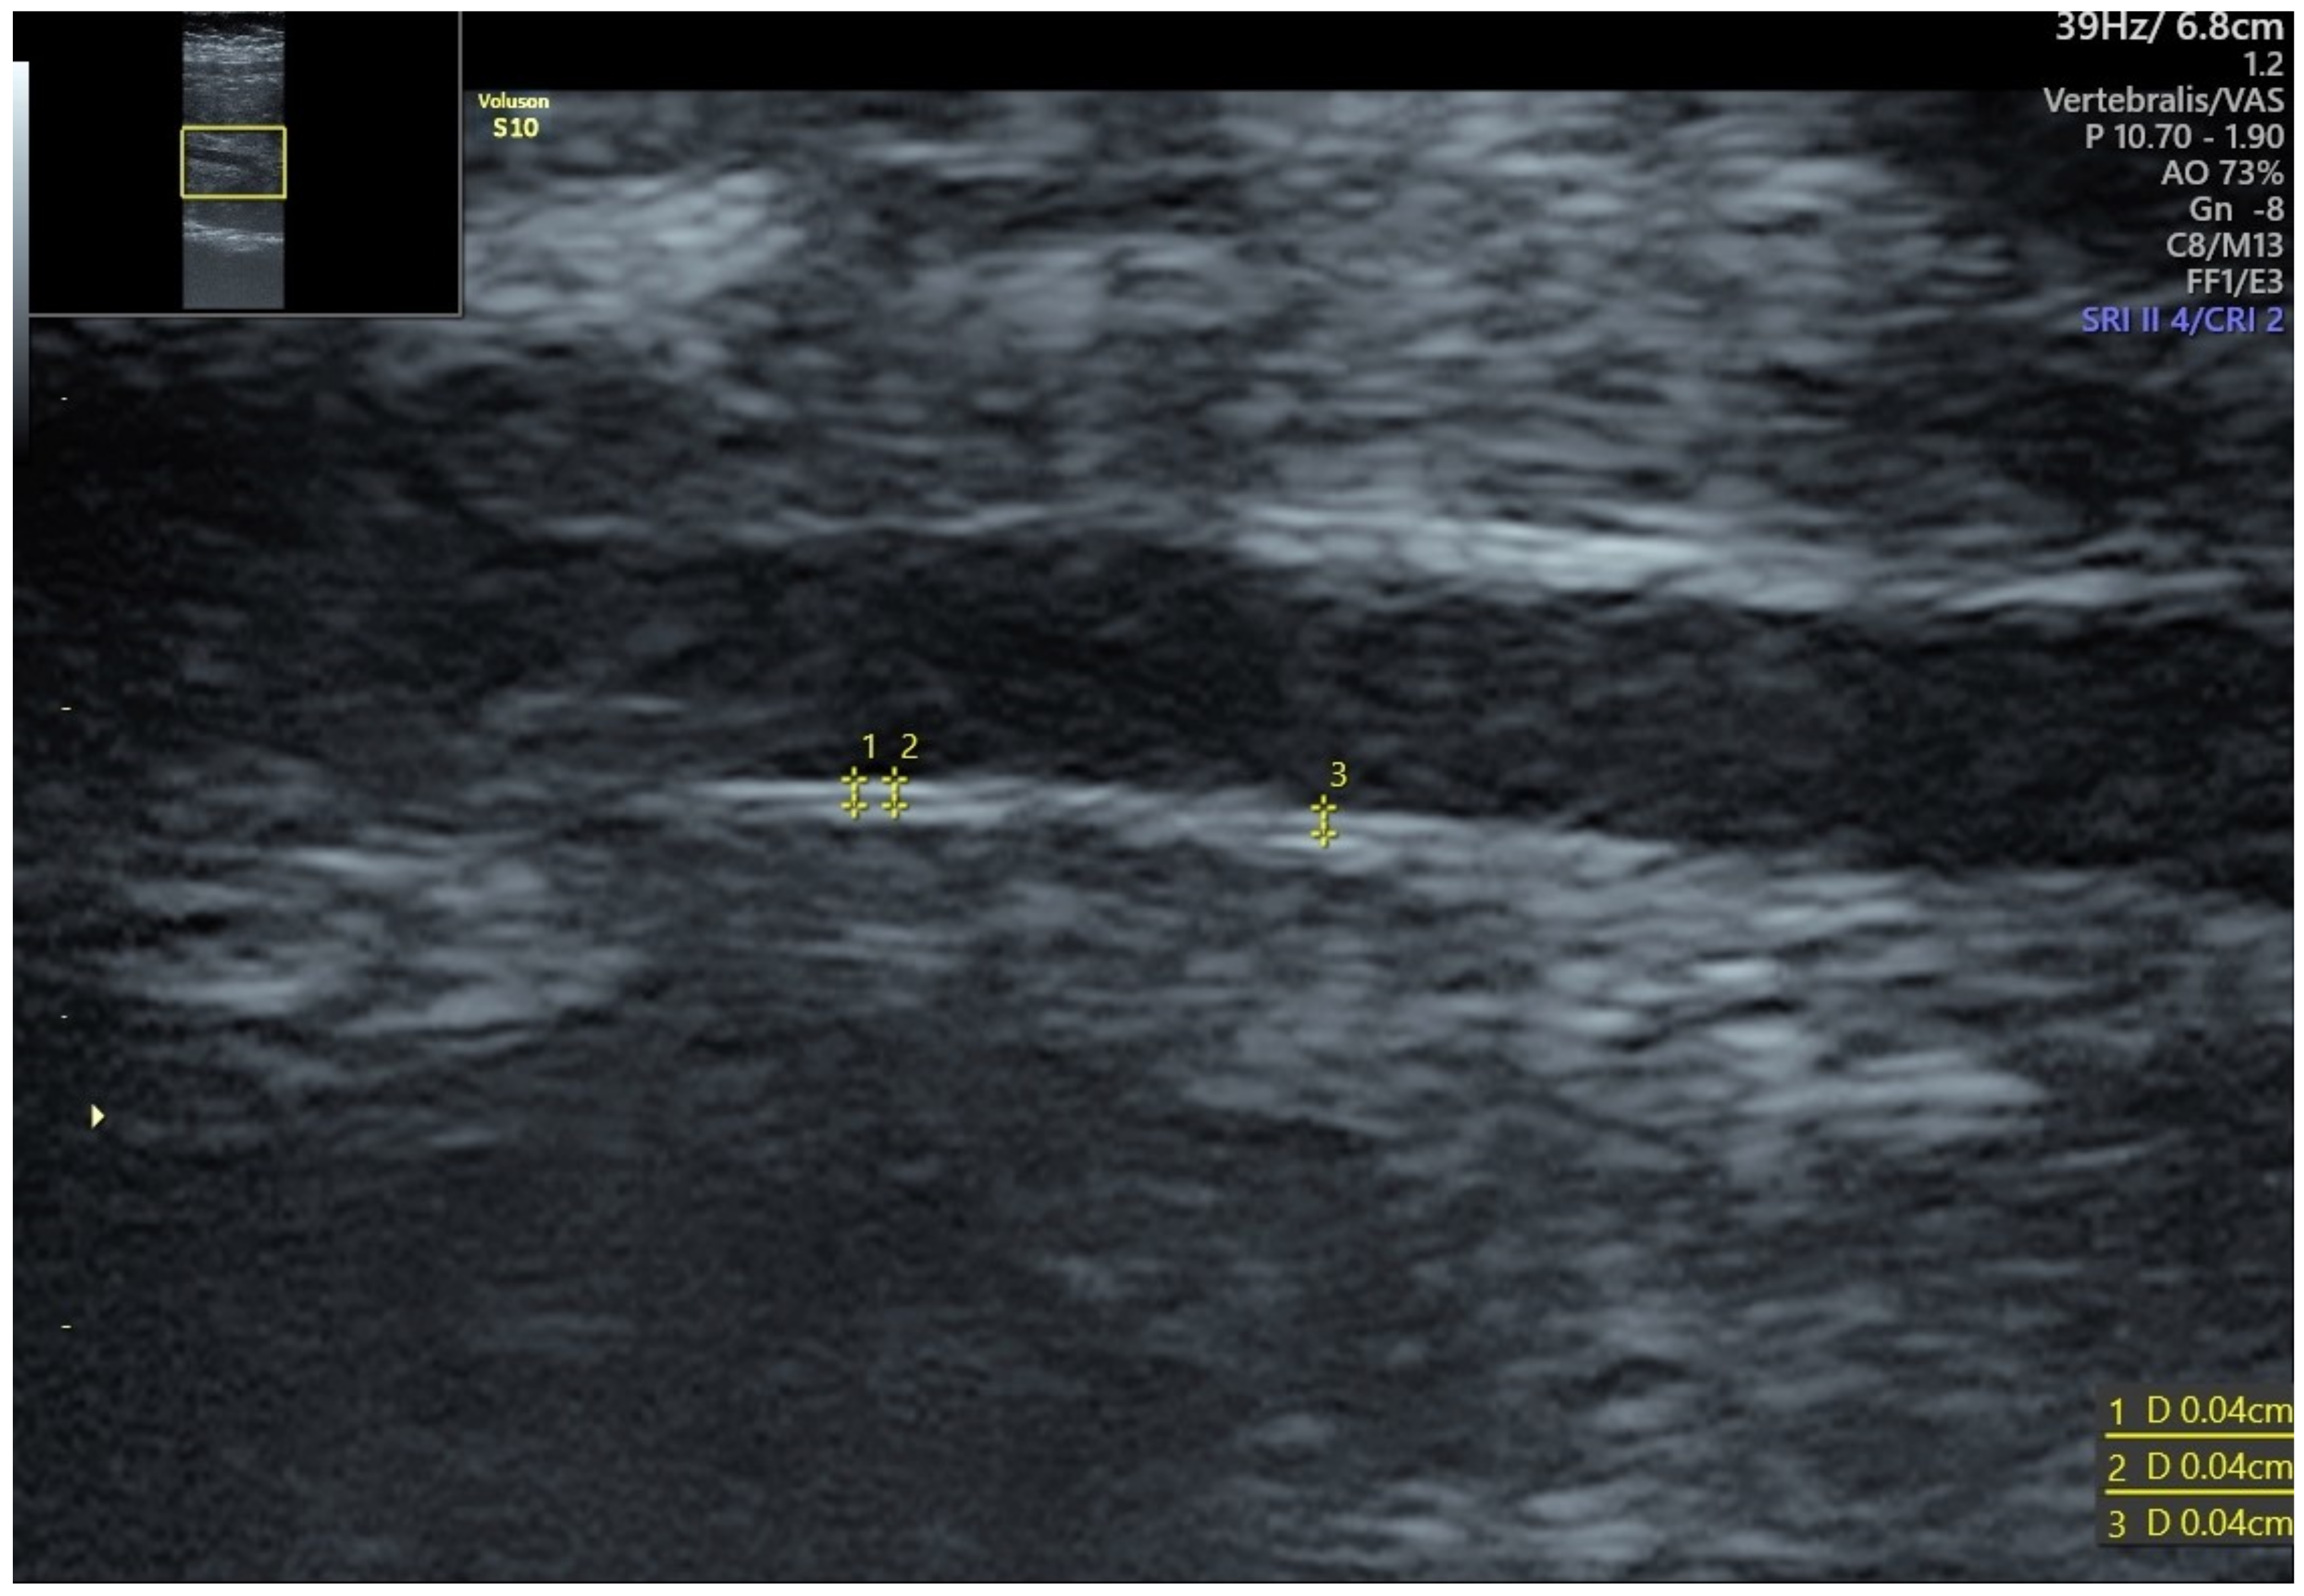

- Evanoff, N.G.; Dengel, D.R.; Narasimhan, S. Assessing Vascular Characteristics of the Fetal Descending Aorta: A Feasibility Study. J. Clin. Ultrasound 2020, 48, 211–215. [Google Scholar] [CrossRef] [PubMed]

- Visentin, S.; Londero, A.P.; Calanducci, M.; Grisan, E.; Bongiorno, M.C.; Marin, L.; Cosmi, E. Fetal Abdominal Aorta: Doppler and Structural Evaluation of Endothelial Function in Intrauterine Growth Restriction and Controls. Ultraschall Med. 2019, 40, 55–63. [Google Scholar] [CrossRef] [PubMed]

- Galjaard, S.; Pasman, S.A.; Ameye, L.; Timmerman, D.; Devlieger, R. Intima-Media Thickness Measurements in the Fetus and Mother during Pregnancy: A Feasibility Study. Ultrasound Med. Biol. 2014, 40, 1949–1957. [Google Scholar] [CrossRef] [PubMed]